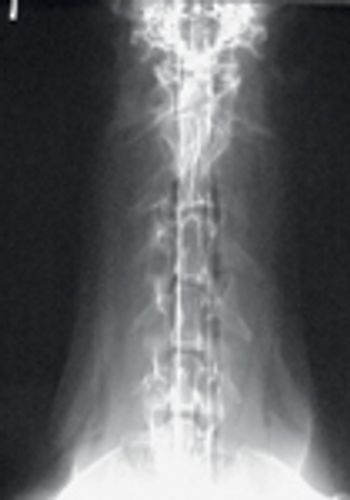

A 65-lb (29.5-kg) 6-year-old spayed female Doberman pinscher was presented for evaluation of a one-month history of progressive left forelimb lameness.